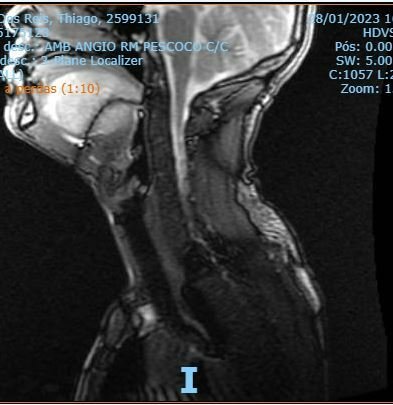

Olá pessoal meu nome é Thiago Reis, em novembro de 2022 comecei a sentir uma pequena bola na minha língua e tive sangramento, preocupado fui procurar ajuda médica, após uma bateria de exames recebi o diagnostico de um Volumoso Tumor nutrido pelas artérias linguais bilateralmente com alta vascularização.. O que identificamos é que a lesão está em 90% da língua, o que dificulta a retirada imediata por causa das sequelas. Como sou um paciente Sintomático e devido a dificuldade de comer já emagreci 13 kg, tive perda de força e inúmeros sangramentos. Meu caso foi para junta médica, e foi indicado embolização vascular cerebral para a redução do tumor e assim após verificar se é possível efetuar a retirada. O meu plano não cobre tudo, e sabemos que infelizmente pelo SUS esse processo será muito demorado e não temos tempo para aguardar pois devido o tumor ser nutrido pelas artérias bilateralmente e com alta vascularização ele está crescendo rápido, então devido a situação de emergência, vou ter que arcar com alguns custos particular. Por não dispor desse valor no momento e meu plano não cobrir tudo estou fazendo essa vaquinha com o intuito de me auxiliar no tratamento, quem puder me ajudar agradeço desde já. Junte se a esse exército do bem. Rumo a maior batalha de minha vida. Qualquer ajuda será bem vinda. Vamos manter a Vaquinha em aberto pois o tratamento é longo e não sabemos qual custo total será necessário. Gratidão um beijo no coração de cada um de vocês.